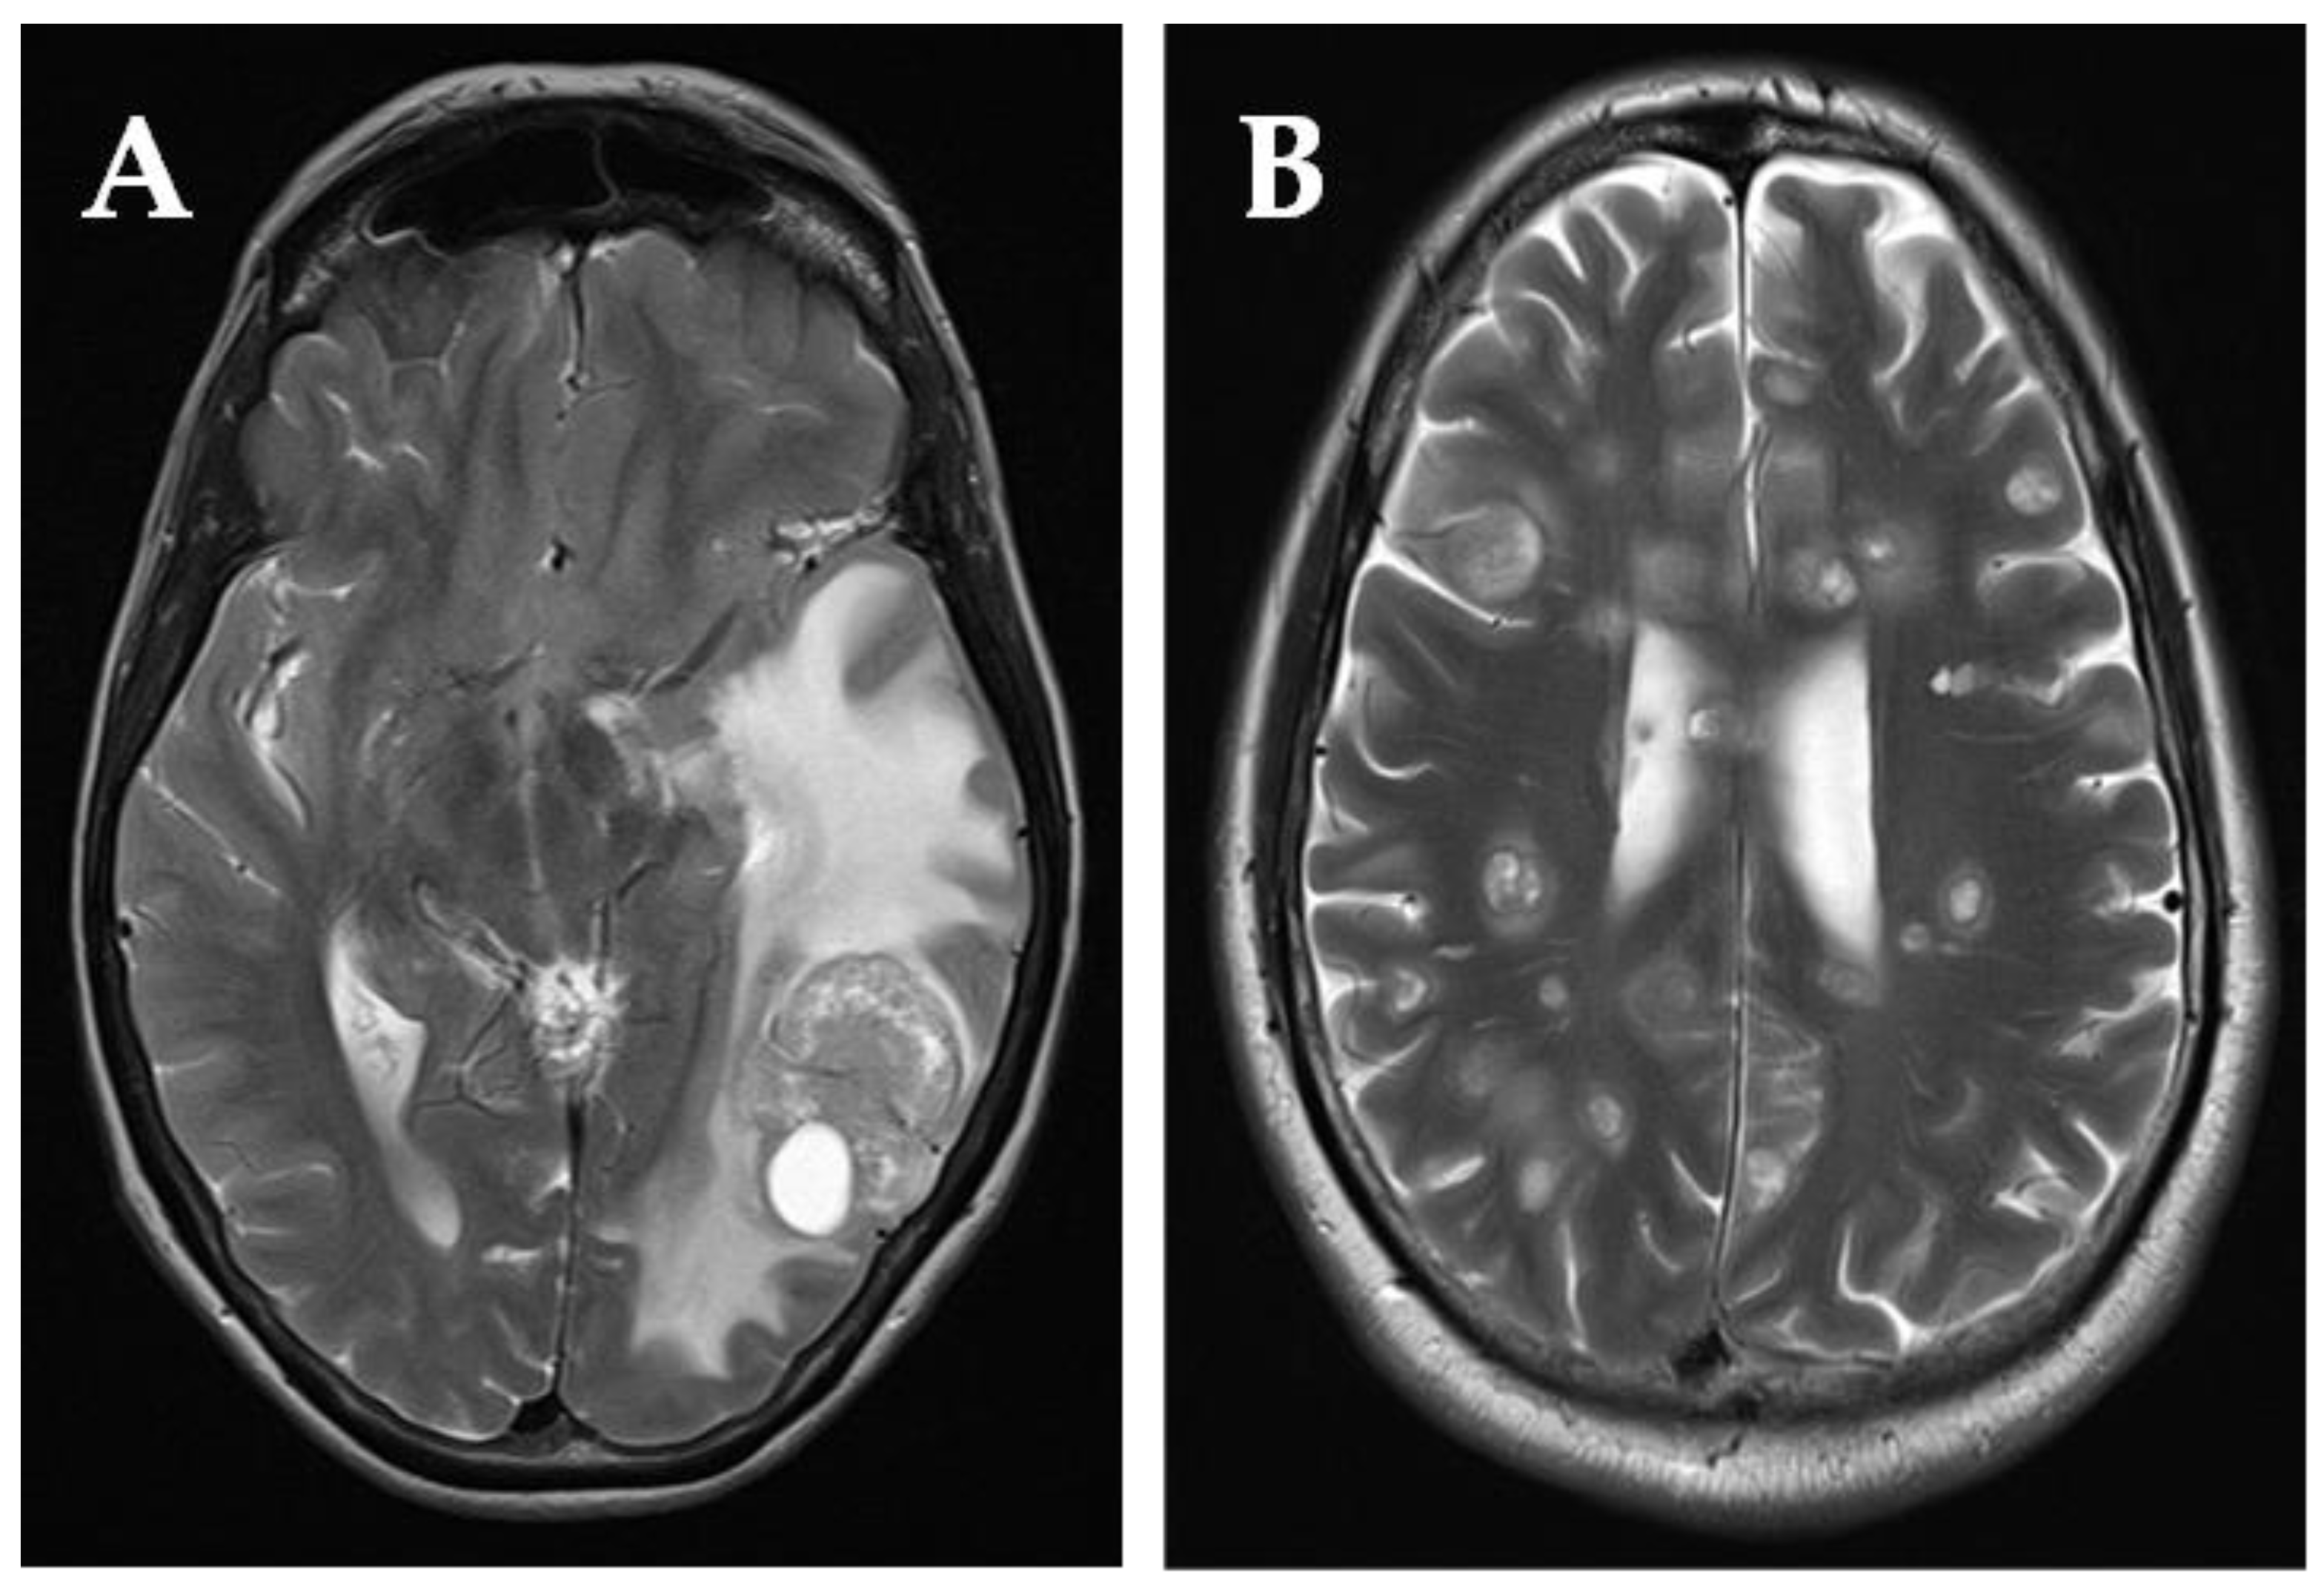

3.3.1. Patients Who Underwent Surgical Resection of BMs